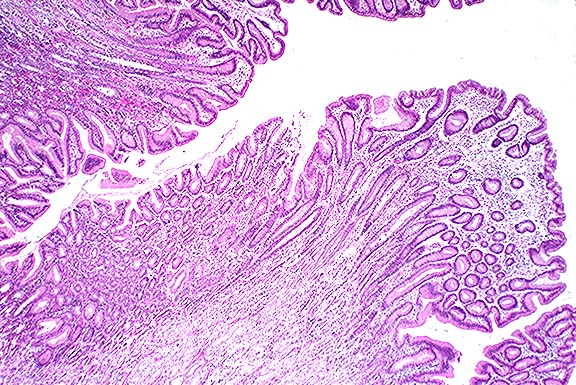

This case was classified as MD because of the diffusely increased mucosal thickness due primarily to foveolar hyperplasia. The section also has numerous glandular cysts, limited inflammation and a normal number of intraepithelial lymphocytes (<16/100 epithelial cells).

Case 5-3. Stomach. Note mucosal hyperplasia with giant folds. 2X

AFIP Diagnosis: Stomach: Hyperplasia, mucosal, diffuse, marked, with mild lymphoplasmacytic and eosinophilic gastritis, baboon (Papio cynocephalus), primate.

Conference Note: The Division of Gastrointestinal Pathology of the AFIP also reviewed this case and agreed that the giant folds are consistent with Menetrier's disease (MD).

In humans, MD is a gastric giant folds disease syndrome, but all parts of the syndrome may not be present at the same time. The full syndrome includes giant folds, gastric protein loss, and decreased gastric acid production, accompanied by a histologic complex that includes foveolar hyperplasia and distortion, glandular atrophy, and edema but little inflammation, in the lamina propria.5 The gastric pits (foveolae) are unusually elongated, and frequently extend from the surface to the base of the mucosa. They occasionally penetrate the muscularis mucosa, ending as cysts surrounded by smooth muscle. The superficial lamina propria is usually edematous, and may contain low numbers of plasma cells and eosinophils.